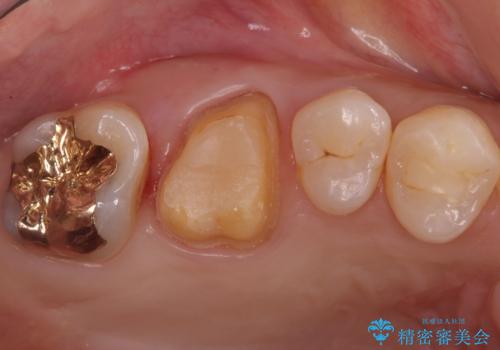

不適な樹脂の詰め物 被せ物で被覆

- 奥歯の劣化・変色した樹脂の詰め物をやり直していきます。

セラミックのインレーでは強度に不安が残るため、セラミッククラウンで全体を被覆することとしました。